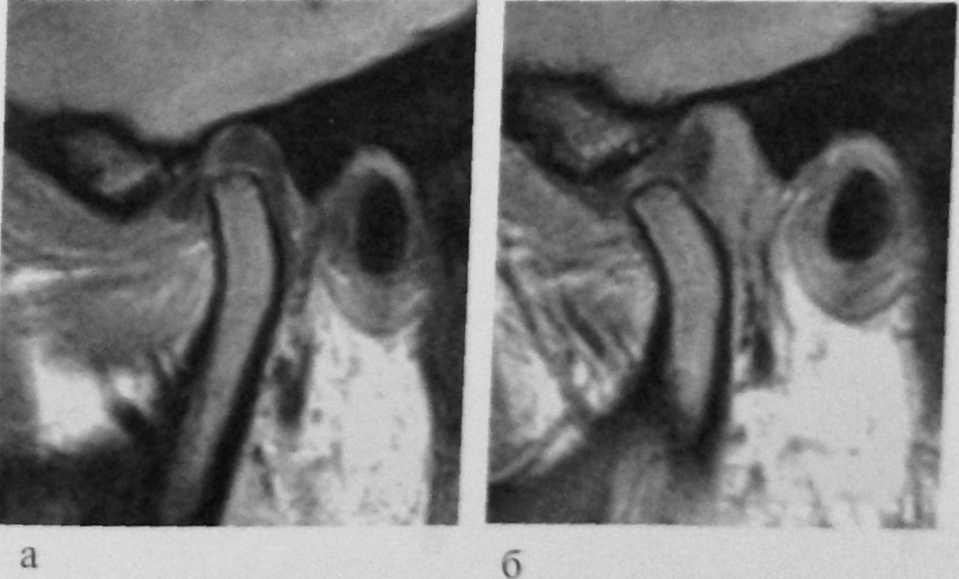

На Т1 взвешенных кососагиттальных томограммах с открытым до 3 см ртом (рис. 8.72) верхушка мыщелка определяется непосредственно под верхушкой суставного бугорка, промежуточная зона диска разобщает верхушки бугорка и мыщелка.

| Рис.8.72. Т1 взвешенная томограмма ВНЧС в кососагиттальной проекции с открытым на З см ртом; 1 - мыщелок нижней челюсти; 2- уставной бугорок височной кости; 3- промежуточная зона диска |

| Рис. 8.74. Т1 взвешенная МРТ ВНЧС в кососагиттальной проекции. Перфорация диска в промежуточной зоне, где диск фрагментарно не визуализируется: а - положение окклюзии; б - максимально открытый рот (ограничение смещаемости мыщелка) |